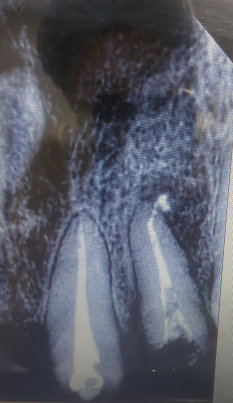

• 9 февраля 2017, в 18:52 Проверенный отзыв

Мой врач сказал, что не нужно удалять. Готовлюсь к протезированию зубов. Зуб чувствительный к холоду, к горячему. Подлежит ли удалению зуб №11 или нет?

Комментарий №171772

• На корне зуба имеется воспаление. Возможно, он простоит с коронкой долгое время, и не будет беспокоить.